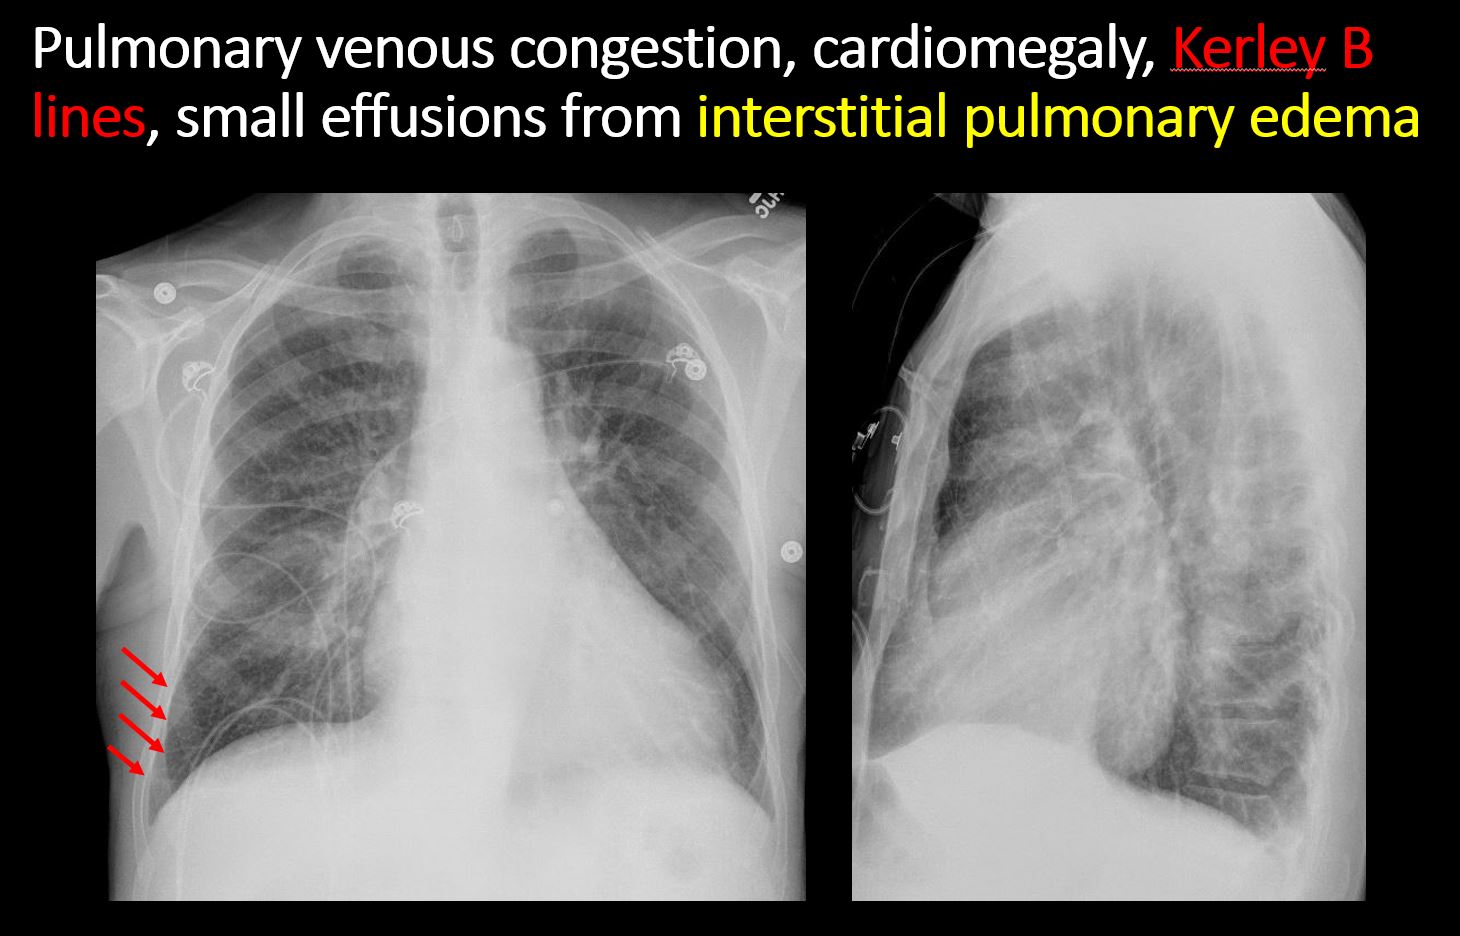

There is enlargement of the cardiac silhouette. [Yes/No]

There is cephalization or haziness of the pulmonary vessels or congestion of the central pulmonary vasculature. [Yes/No]

There is focal or diffuse interstitial disease. [Yes/No]

There is a pleural effusion, blunting of the costophrenic angle, or posterior sulci. [Yes/No]